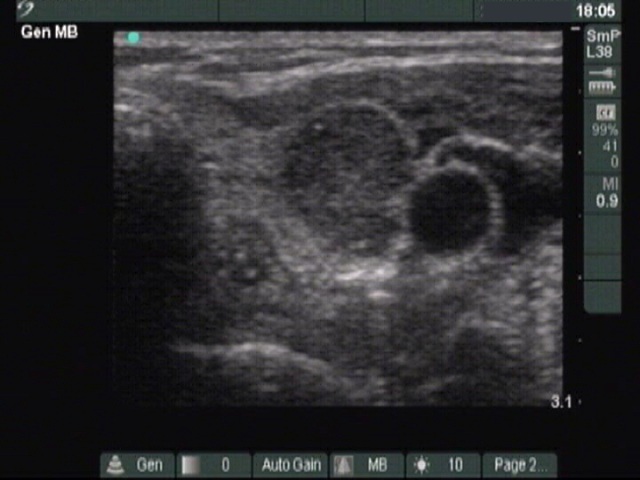

Ultrasonography: There were three hypoechogenic lesions wich has hyperechogenic granules larger than foci of microcalcification. There was a lymph node above the left lobe. The node lacked a regular hilum and was round

Comment. The coarse and large hyperechogenic figures seen on ultrasonography correspond to amyloid deposits. In contrast with coarse calcification, there is no acoustic shadow dorsal to amyloid. The foci of amyloid are much larger than a microcalcification. The specificity of this type of hyperechogenic figures is around 50%.